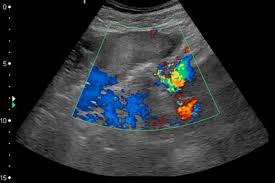

Часто доплером называют еще вот этот "режим цветных пятен":

Это тоже кровотоки в режиме доплера. Многие УЗИсты просто смотрят именно этот режим доплера и сообщают вам, что все хорошо. Не ведитесь! Информации о скорости кровотоков такое исследование не несет.